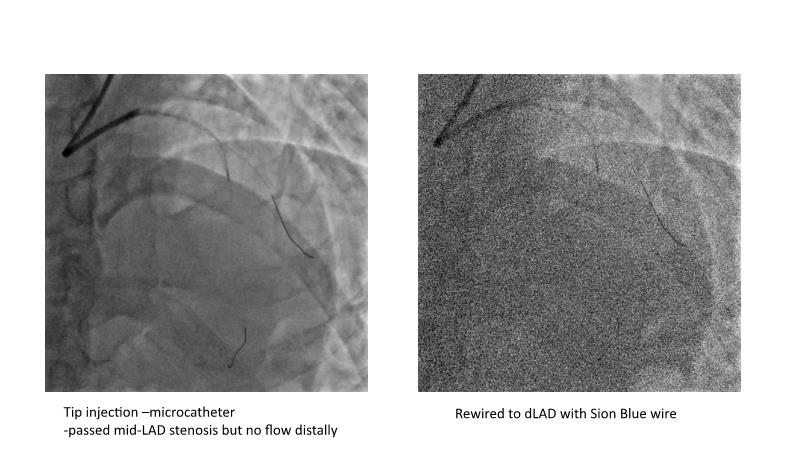

This session is recommended for you if you are seeking insights into the advantages of using IVUS imaging over visual assessment for better outcomes in left main bifurcation procedures. Discuss with experts the benefits of using RotaCUT in lesion preparation for left main bifurcation and explore the impact of high radial strength stents on the procedure's success.

• To see advantages of RotaCUT as part of lesion preparation in left main bifurcation